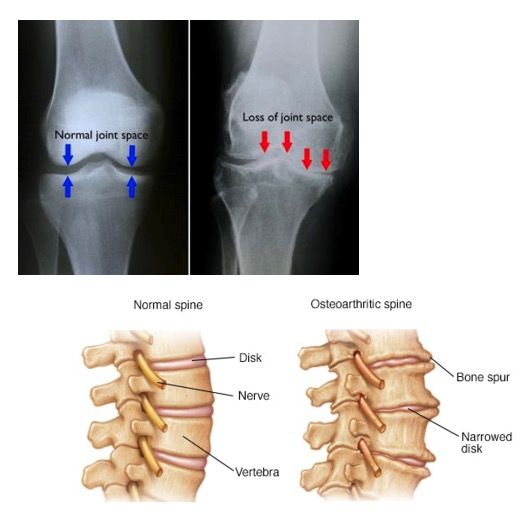

Osteoarthritis is degeneration in a joint. It can occur in any moveable joint in the body, including the spine, hips, knees and fingers. Osteoarthritis occurs over a long period of time and is more likely to occur in joints that have had a previous injury. It also occurs in joints that have altered biomechanics and thereby change how the joint is loaded. As we age most people will develop osteoarthritis in joints in their bodies.

Osteoarthritis can present as slight swelling in the joint, pain with movement of the joint, and stiffness of the joint, especially after inactivity. Patients also notice a loss of flexibility and tenderness. They may also have a grating sensation when moving the joint.

On X-ray, a joint with osteoarthritis will present with loss of joint space (which is loss of cartilage in the joint) and spurs will often develop in response to the loss of joint space in an effort to stabilise the joint. It is not common for X-ray features to correlate to the symptoms a patient is experiencing.